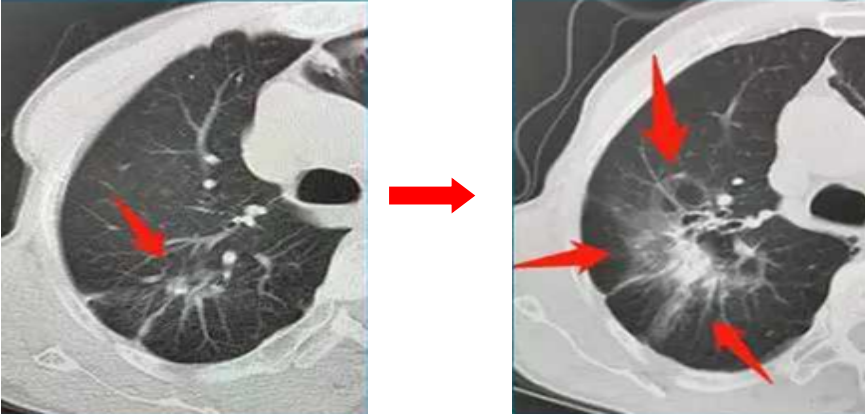

55歲的張先生兩年前查體發(fā)現(xiàn)了肺結(jié)節(jié),認(rèn)為自己既不抽煙,也不熬夜、酗酒,更沒(méi)有什么癥狀,應(yīng)該沒(méi)什么事。醫(yī)生建議他每3個(gè)月復(fù)查一次CT,他置之不理,認(rèn)為自己好端端的,干嘛還浪費(fèi)那錢。結(jié)果兩年后出現(xiàn)咳嗽胸痛才想起來(lái)就診,發(fā)現(xiàn)原來(lái)5mm的肺結(jié)節(jié)已經(jīng)長(zhǎng)大了(見(jiàn)下圖),還出現(xiàn)了轉(zhuǎn)移,診斷為晚期肺癌,悔之晚矣。